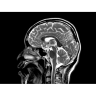

МР-томограф с широким туннелем Optima MR450w является настоящей рабочей лошадкой и может эффективно обслуживать большее число пациентов. Томограф обеспечивает одновременно удобство пациента, продуктивность работы, отличное качество изображения. В этой МРТ-системе инженерам компании удалось без компромиссов совместить необходимый объем перемещения с удивительно высоким качеством изображения.

Благодаря принципиально новым технологиям мы расширили возможности МР-томографов с широкими туннелями, совместив непревзойденное качество изображений с высокой производительностью при широком — 50 см — поле зрения.

МР-томограф Optima MR450w позволяет получать изображения исключительно высокого качества, которые помогают установить диагноз. Чтобы удовлетворить ожидания клиентов в отношении высокого качества, в МР-томографе Optima MR450w были сохранены дополнительные возможности платформы Discoverу, привнесшие в его работу универсальность и мощь.